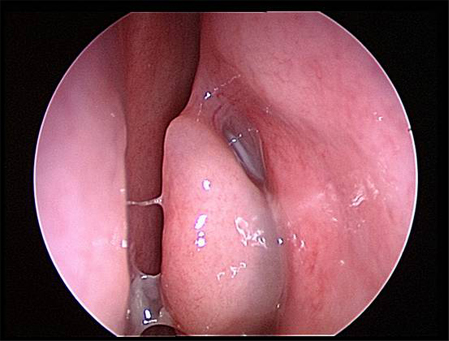

Peri-orbital or malar oedema, orbital proptosis, visual disturbances, abnormal extra-ocular movements, or abnormal neurological signs may indicate the presence of complications, and urgent otolaryngology consultation is required.[Figure caption and citation for the preceding image starts]: Right inferior turbinate and septum are visible prior to decongestant sprayFrom the collection of Melissa Pynnonen, MD [Citation ends].

The nasal cavity should be examined for the presence of mucosal erythema or purulent discharge. Optimal examination is performed after topical decongestant spray.[18] Either an otoscope or a nasal speculum and head light may be used. However, because nasal examination may be difficult or the signs non-specific, nasal endoscopy is recommended in selected patients, including patients refractory to empirical antibiotic therapy or where there is concern for antibiotic resistance, or in immunocompromised patients.

Endoscopy can provide excellent visualisation of the nasal cavity and sinus drainage paths. There are two types of endoscope: rigid and flexible. A rigid nasal endoscope has superior resolution and only requires the use of one hand. This easily allows cultures of the nasal cavity or sinus to be obtained if necessary. A flexible nasal endoscope is more comfortable for patients, but requires both hands to use. There are flexible nasal endoscopes that have a channel for collecting cultures, but these tend to be larger and more uncomfortable and they are also more difficult to re-process. Generally, the flexible nasal endoscope is preferred in children as it is better tolerated; however, either type may be used in adults and children. Choice will depend on the practitioner's familiarity with the procedure, and most will be performed by an ear, nose, and throat specialist.